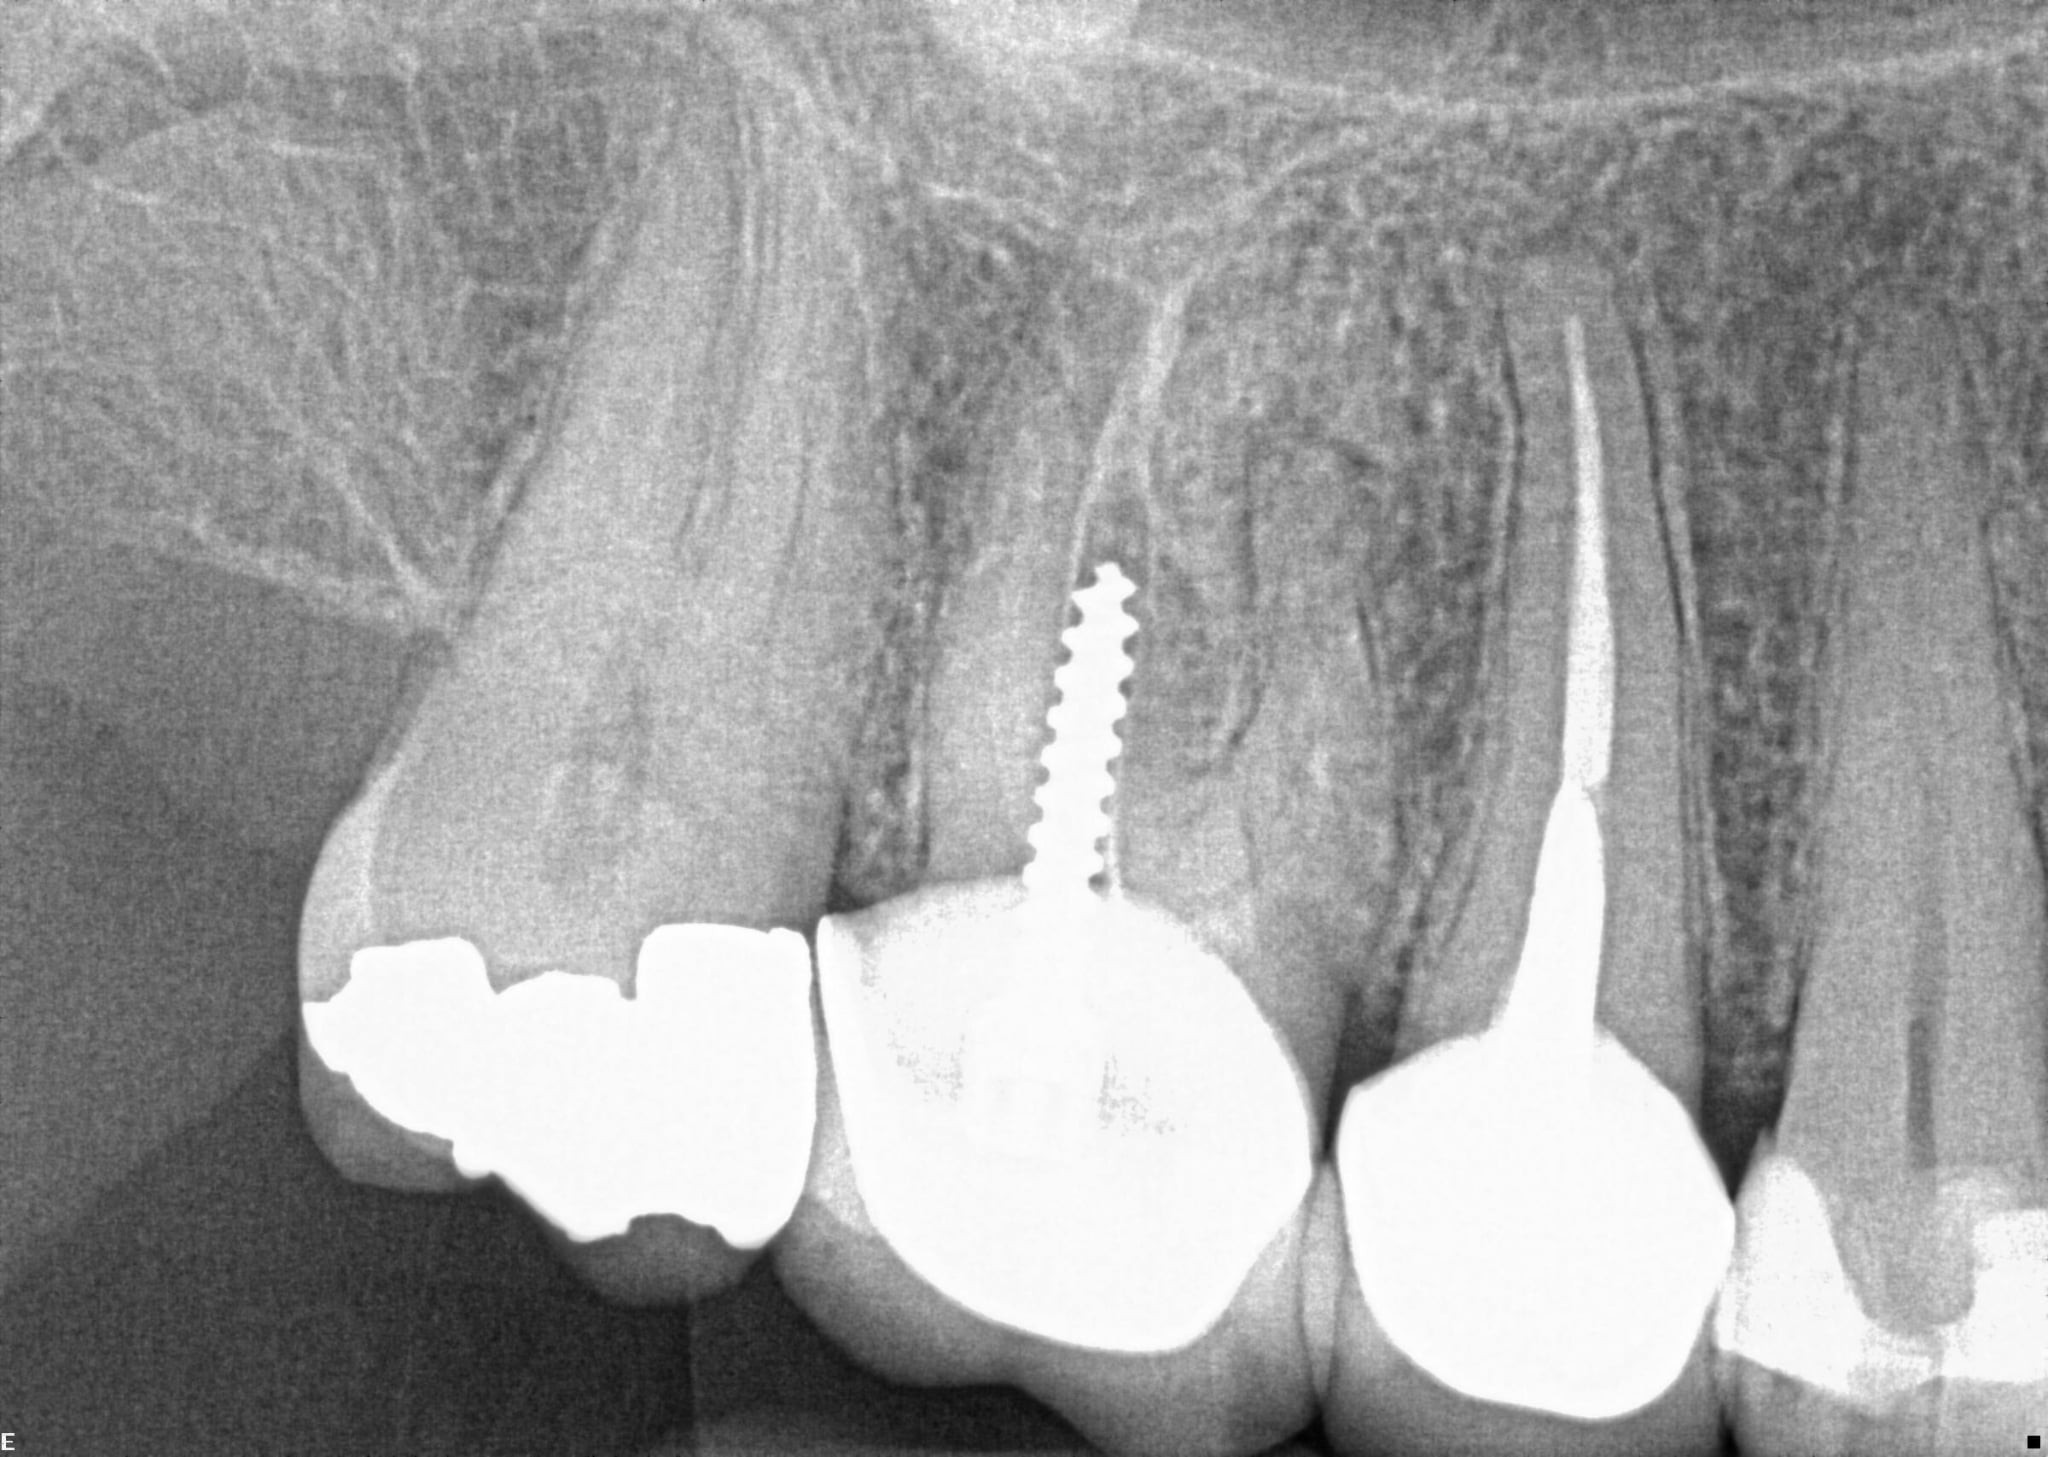

1.  What option can describe the post placement in the X ray bellow for the tooth # 2.5?